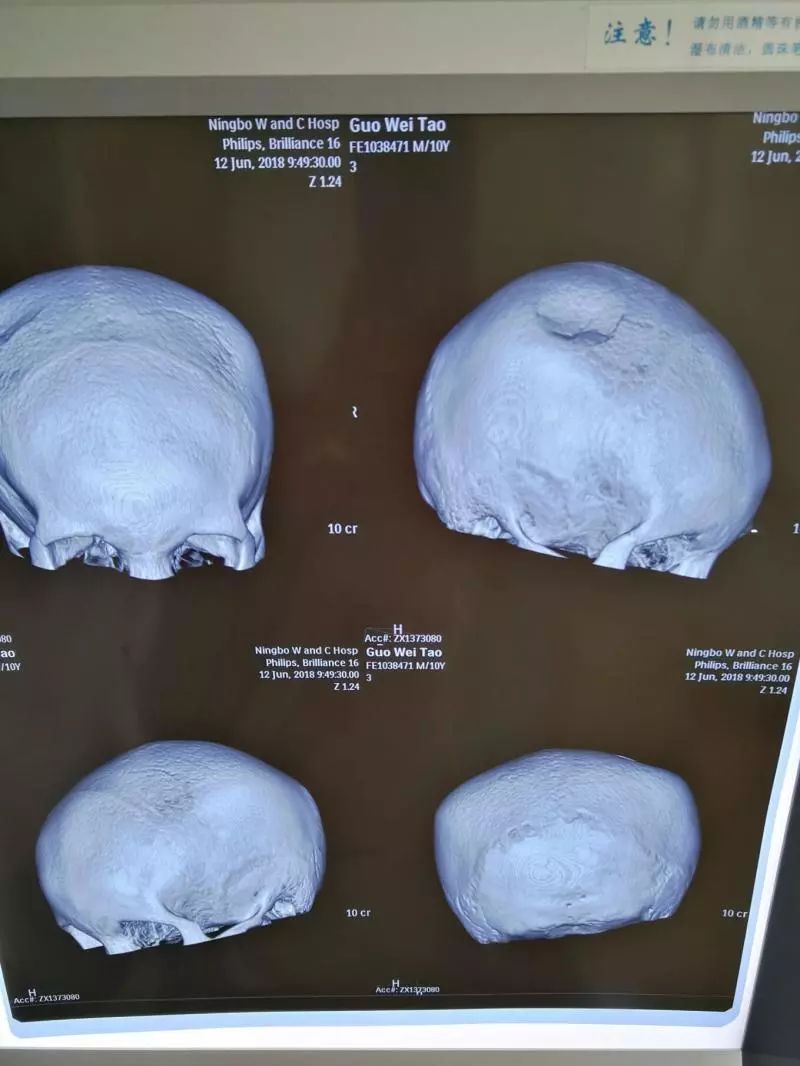

头颅CT显示,浩浩头骨被砸出一个乒乓球大小的坑,深度超过1厘米,伤处的脑组织也受到挤压陷了进去,“颅内高压,需要立即手术!”接诊的小儿神经外科主任医师石坚说,浩浩受伤的是顶部运动区,不立即手术的话,相应脑功能或出现不可逆损害,继发偏瘫、癫痫就麻烦了。

拍片显示,浩浩头部被砸出一个坑,脑组织也受到了压迫。